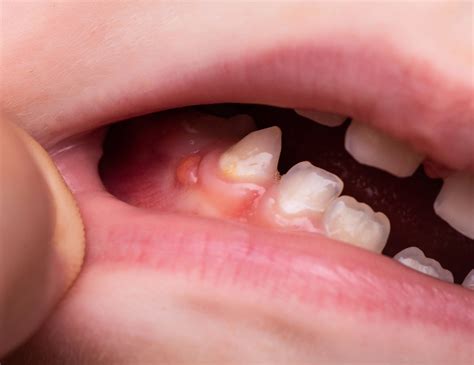

Una fístula dental es una pequeña abertura o canal anormal que se forma en la encía o en la región cercana a la raíz de un diente infectado. Llamamos fístula dental al canal que se origina desde la zona infectada de un diente hasta la superficie exterior de la encía. Una fístula dental es una afección oral que implica la formación de un conducto anormal entre el diente y el exterior de la boca. Esta conexión anormal se crea como resultado de una infección dental que ha progresado y se ha extendido más allá de la raíz del diente, formando un absceso.

La fístula actúa como un conducto de drenaje para permitir que el pus y los desechos de la infección se eliminen del cuerpo. En ese canal se acaba depositando pus y, conforme se llena, se crea una protuberancia o grano próximo a las encías. Es el propio organismo quien crea esta fístula, y lo hace tras detectar una infección dental.

¿Te ha aparecido un bulto en la encía? ¿Sabías que puede tratarse de una fístula dental? Una fístula dental es un pequeño bulto que aparece en la encía o el paladar como consecuencia de una infección oral. Con menos frecuencia, también puede surgir en la cara o el cuello. Asimismo, se caracteriza por la supuración de pus. Por último, puede ir acompañada de dolor o fiebre.